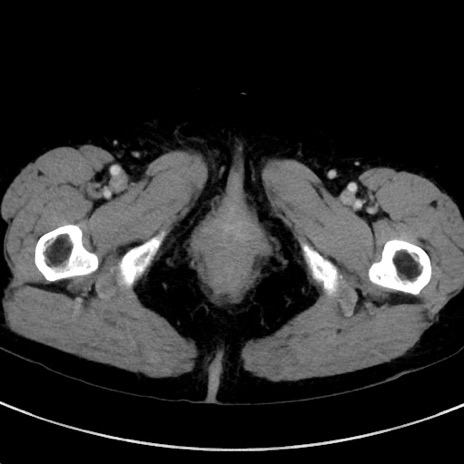

症例23(横断像)

【症例】70歳代女性

【主訴】下腹部痛・嘔吐

【現病歴】2日前より腹痛あり。昨日嘔吐あり。症状改善しないため来院。

【既往歴】胃GISTに対して胃部分切除後。

【身体所見】BT 37.1℃、BP 128/77mmHg、腹部:平坦・軟、下腹部に圧痛あり。

【データ】WBC 10200、CRP 0.31